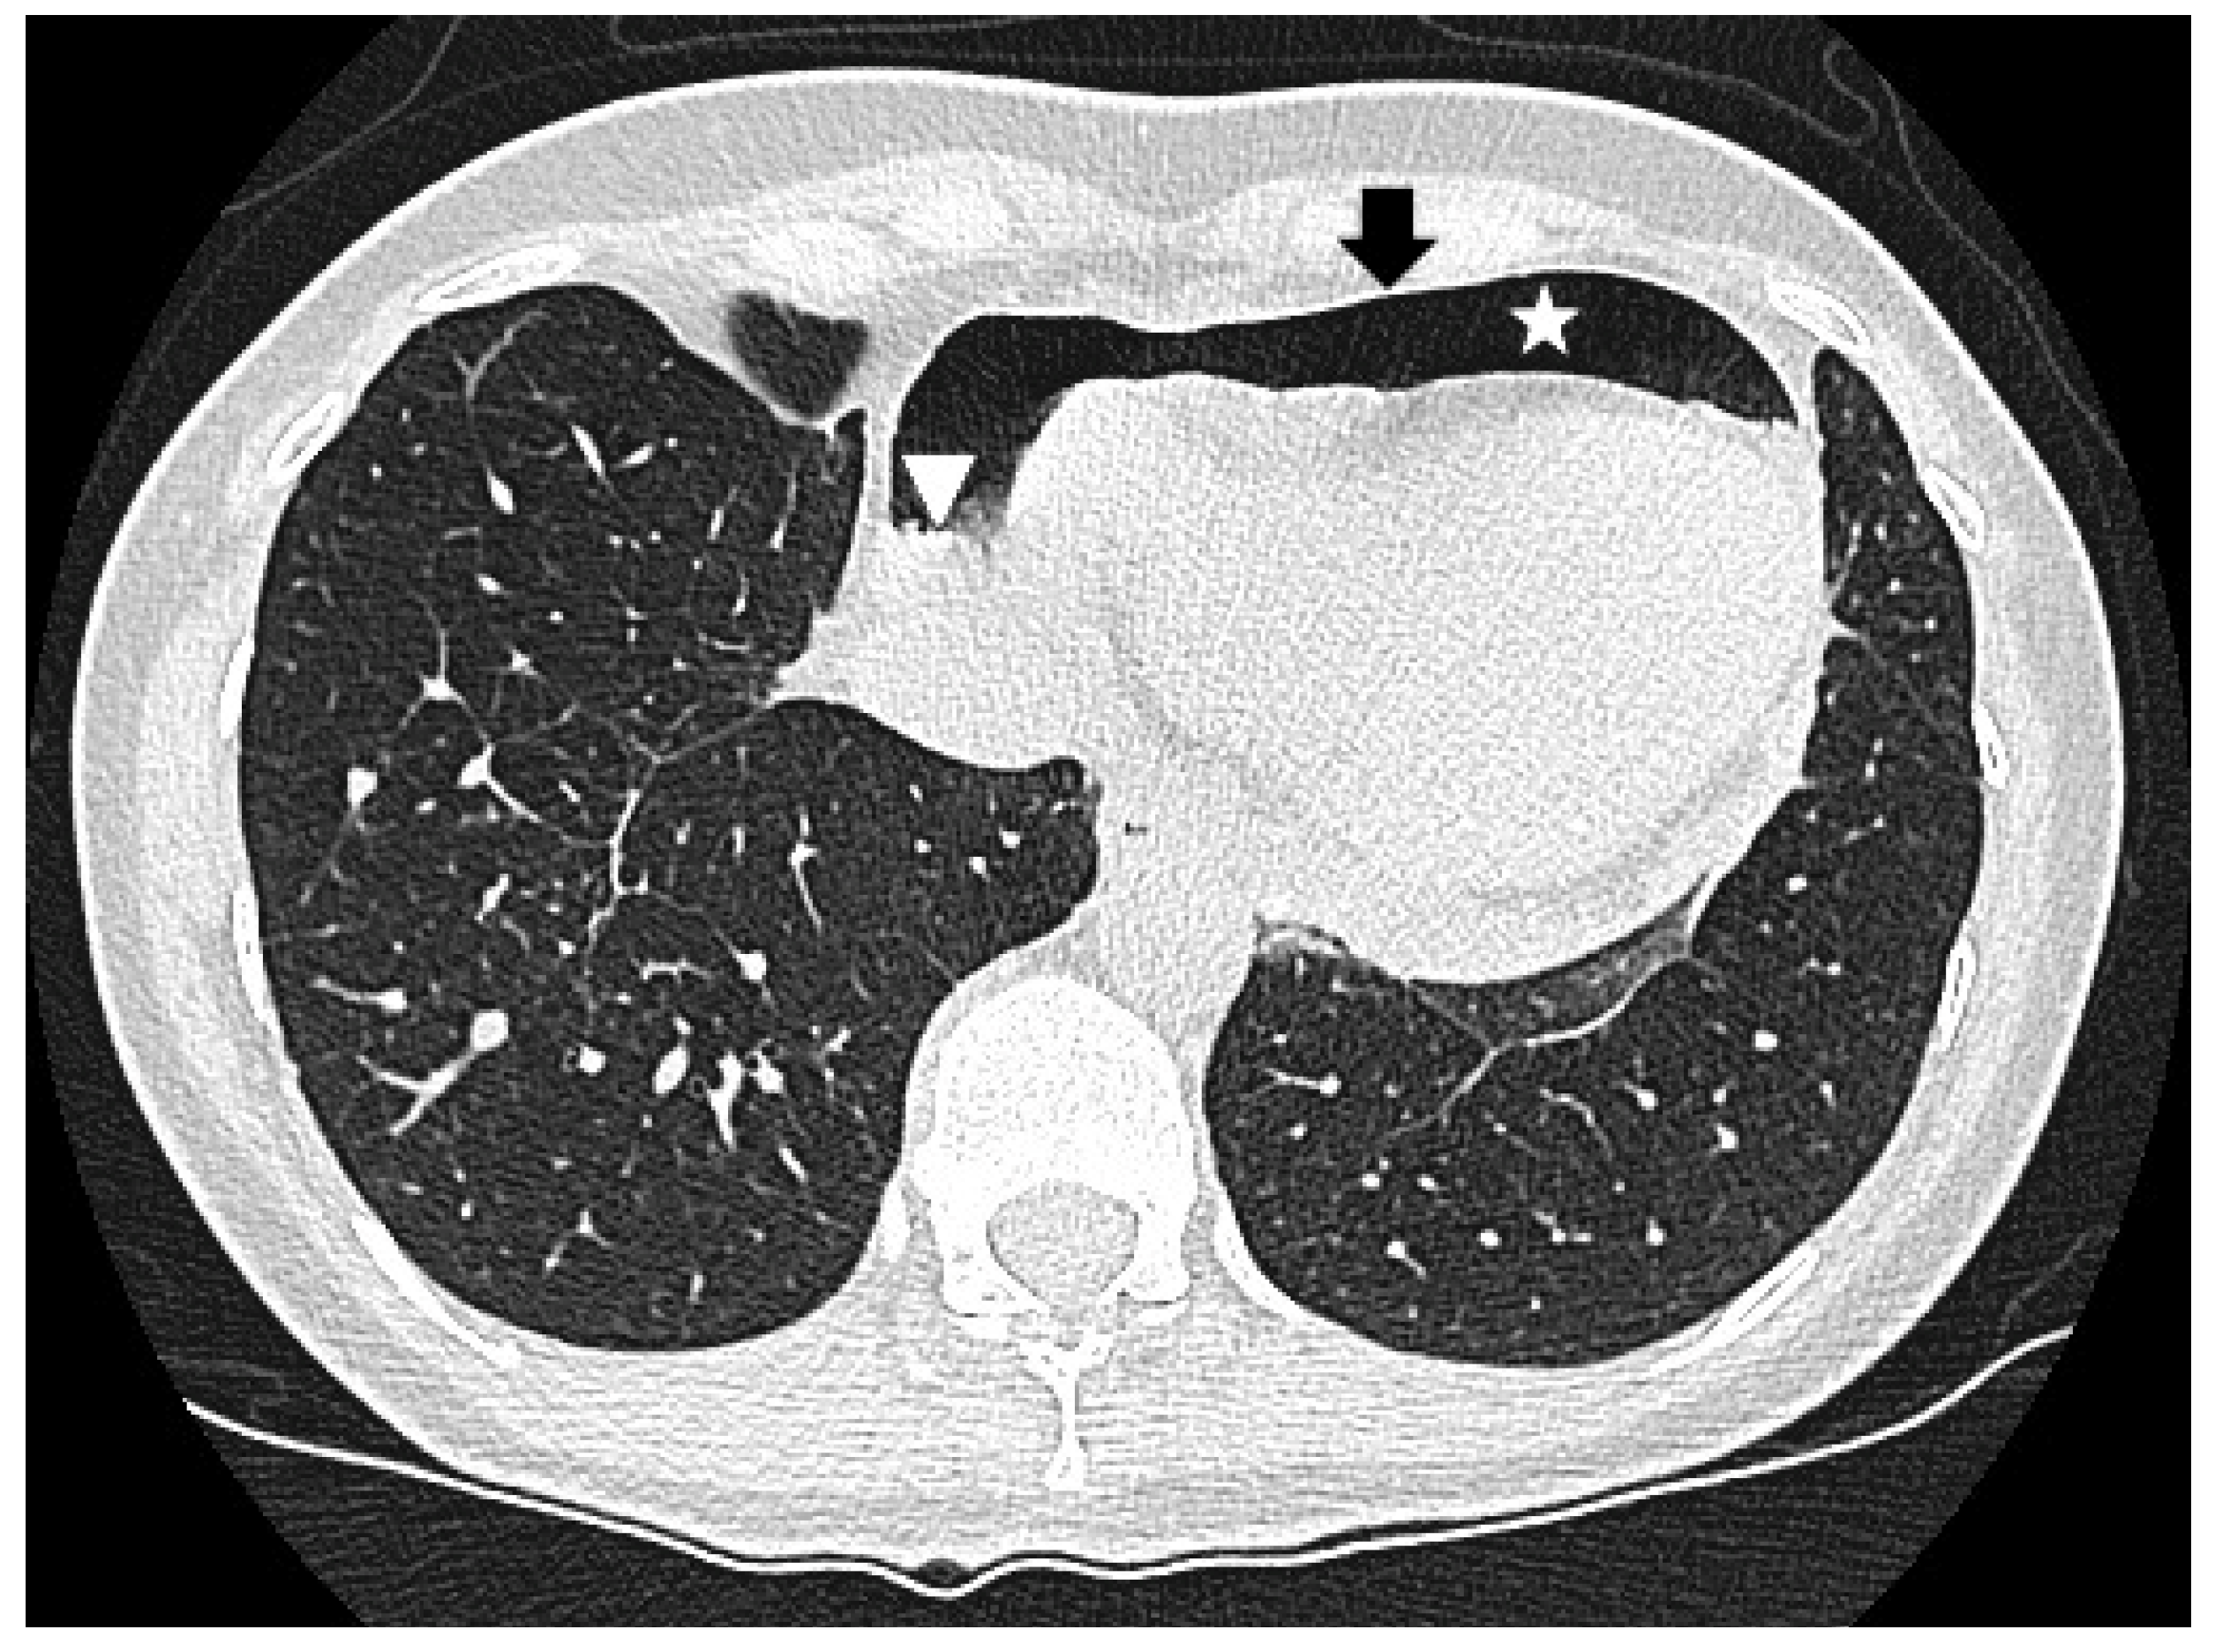

2. Case Report